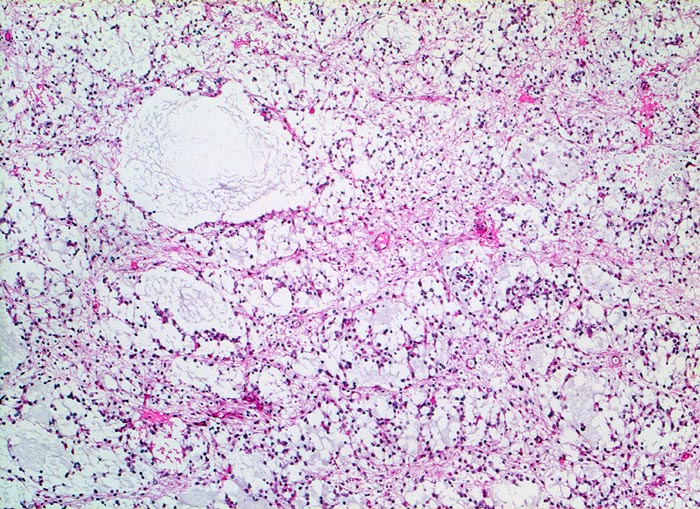

PathoPic ID 5256 - Oligodendrogliom (WHO Grad II)

Oligodendrogliom (WHO Grad II)

maligner Tumor

Hirn frontal

Nervensystem

Fokale mukoide/zystische Degeneration innerhalb des Tumors mit Ausbildung von

Pseudozysten.

Kopfschmerzen und epileptische Anfälle seit zwei Jahren.

Histologie

50

59

männlich